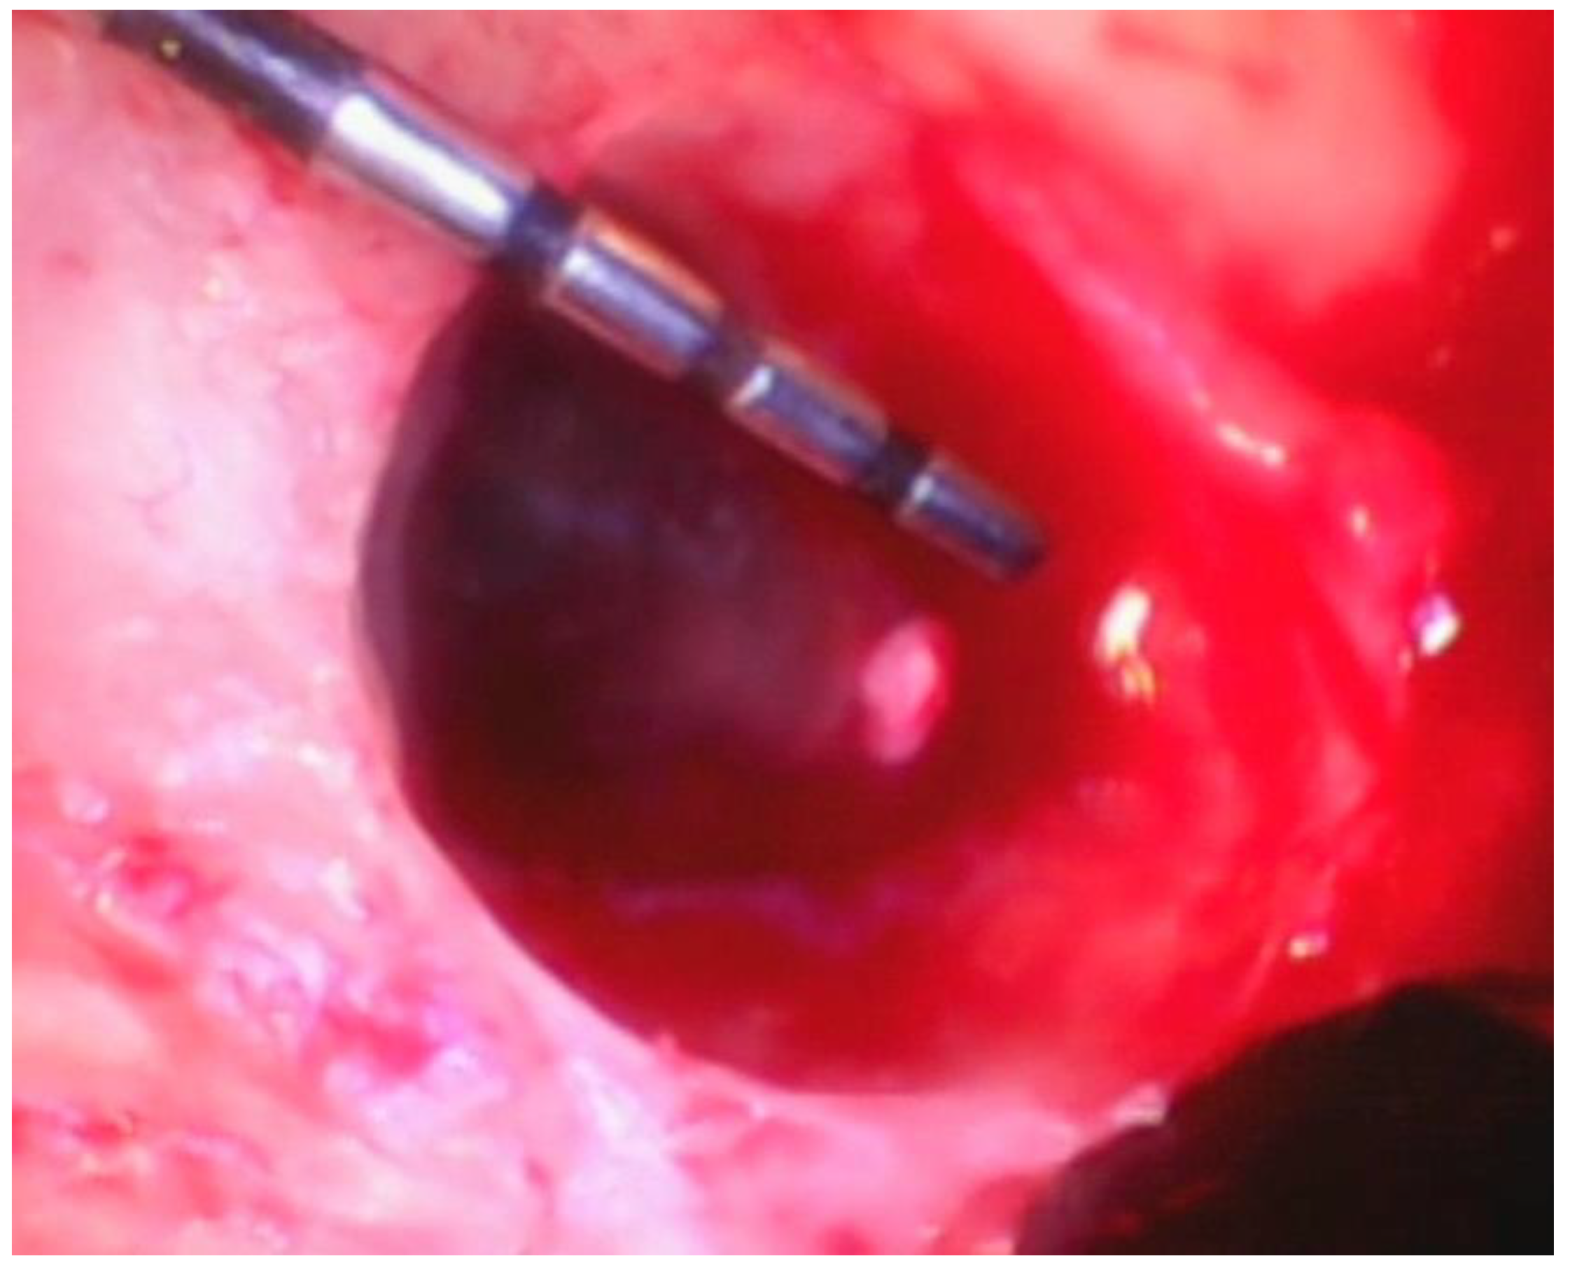

Following the removal of the thin section of tissue, any granulation tissue is removed in a similar manner as performed on natural teeth. However, care should be taken to not touch the implant surface with the instrument used to remove the granulation tissue. The implant surface is covered by titanium oxide, and this has been shown to be an integral part of the osseointegration process [22]. Titanium oxide is very fragile and will be damaged or corroded if the implant surface is touched by an instrument or disinfected with harsh chemicals such as citric acid or a tetracycline solution. Because of this, great care is taken to not touch the implant with a curette while removing the granulation tissue and to only gently wipe the implant surface with sterile gauze soaked in saline. The debrided peri-implant bone loss is shown in Figure 8.

Figure 8. The fully debrided bony lesion can be visualized after removal of the granulation tissue.